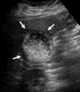

Acute cholecystitis

Cholecystitis is inflammation of the gallbladder. Symptoms include right upper abdominal pain, nausea, vomiting, and occasionally fever. [Source: Wikipedia ]

Echo within gallbladder

Pericholecystic fluid